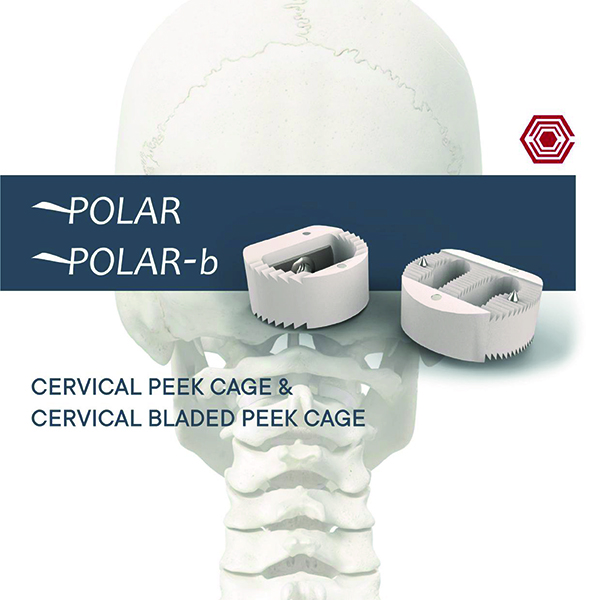

Polar

Akif Kaya Aybek

Norm Akademi

- Surgical Technique

- Sizes

- Instrument Container

- Intrument Types